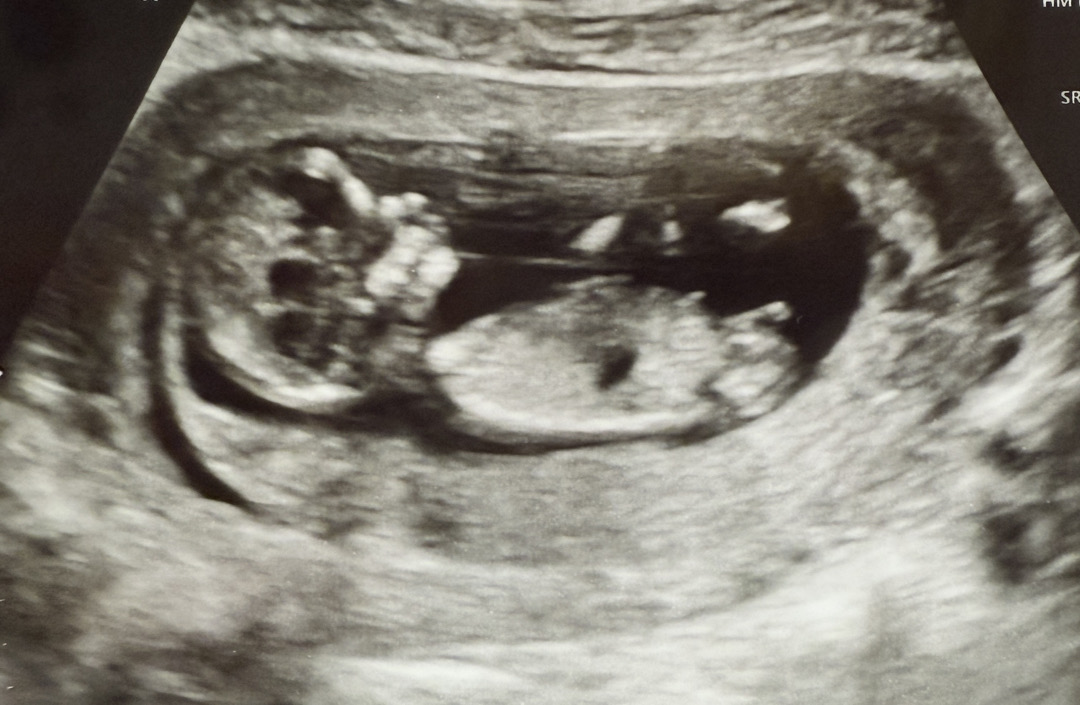

12주4일차 각도법 어때보이시나요??

건강하게만 나오면 바랄게 없지만 그래도 궁금하고 설레네요 !! ㅎㅎ

딸같아요!!

딸같은데요???!??!?